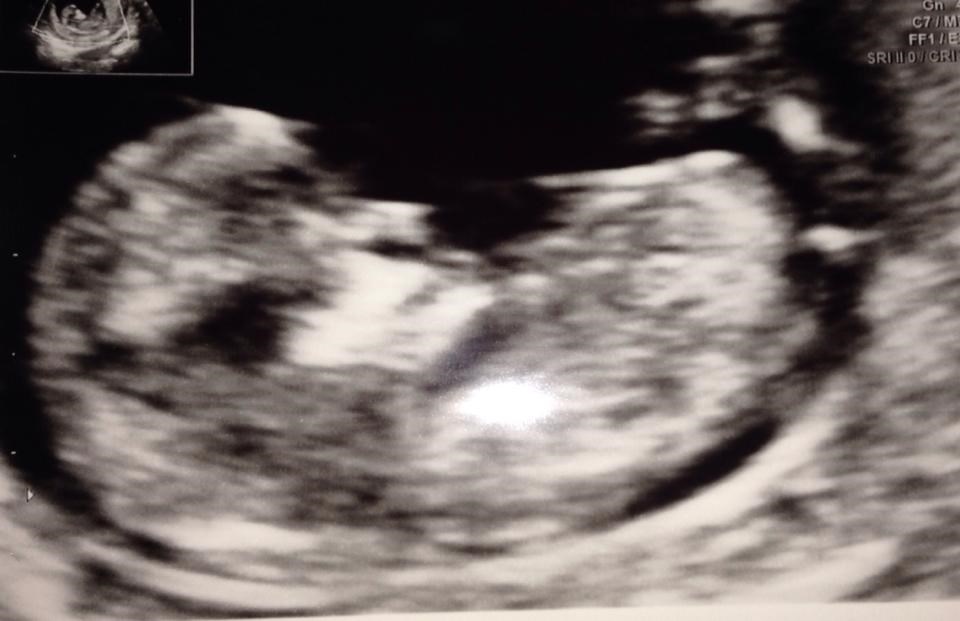

Var til NF onsdag, hvor jeg fik fastsat termin til 4/10

Desværre betød det så at min blodprøve ikke kunne bruges da den var taget for tidligt, øv! Men fik at vide at nakkefolden havde normal størrelse, så hun tvivlede på det ville være dårlige tal, men over med mig og få taget ny blodprøve.

I dag ringer sygehuset så og fortæller om tallene, som hedder 1:>20.000, jeg kan simpelthen ikke få bedre tal :')

ps, i skal da ikke snydes for et billede på trods af jeg er anonym